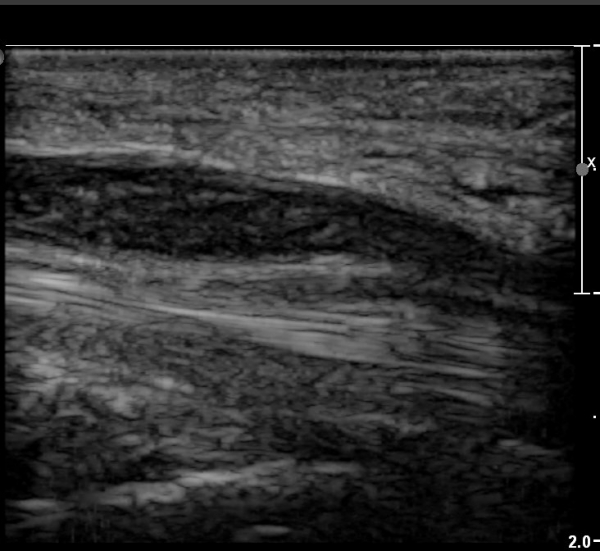

ÇÏŰ½ºÆ½(°íÁÖÆÄ) ŽÃËÀÚ¸¦·Î °üÂûµÈ ¸ð½À¿¡¼­ Á¤Áß½Å°æ ºÎºÐ ½Å°æ´Ù¹ßÀÇ Àú¿¡ÄÚ

º¯È­°¡ ¶Ñ·ÈÇÔ(»çÁø 6, 7).

Á¤Á߽Űæ Á¾´Ü¸é°Ë»ç¿¡¼­µµ ¼Õ¸ñ ¸»´ÜºÎ¿¡¼­ ¼ö±Ù°ü ±ÙÀ§ºÎ±îÁö À̾îÁø Àú¿¡ÄÚ

Á¾¾çÀÌ °üÂûµÊ(»çÁø 8, 9, 10, 11).